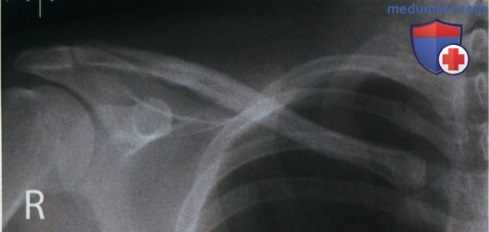

РИСУНОК 1 Рентгенограмма ключицы в аксиальной ПЗ проекции, демонстрирующая ее правильное положение. РИСУНОК A Рентгенограмма ключицы в ПЗ проекции. Пациент повернут в противоположную сторону от исследуемой ключицы. РИСУНОК B Рентгенограмма ключицы в ПЗ проекции. Пациент повернут в сторону исследуемой ключицы.

• Медиальный конец ключицы находится вблизи латерального края позвоночного столба (рис. А и B)

• Верхний угол лопатки визуализируется на 1,25 см ниже ключицы

• Медиальный конец ключицы накладывается на первое, второе и третье ребра

• Средняя и латеральная трети ключицы визуализируются выше акромиального отростка, ключица изогнута вверх (рис. 3 и 4)

• Середина ключицы находится в центре экспозиционного поля

• В экспозиционное поле входят ключица и акромиальный отросток

РИСУНОК 3 Рентгенограмма ключицы в ПЗ проекции: перелом. РИСУНОК 4 Рентгенограмма ключицы в аксиальной ПЗ проекции: перелом.

а) Ротация туловища. Если при рентгенографии ключицы в аксиальной ПЗ проекции туловище повернуто в противоположную сторону от исследуемой ключицы, на рентгенограмме медиальный конец исследуемой ключицы будет накладываться на позвоночный столб (см. рис. А).

Если при рентгенографии ключицы в аксиальной ПЗ проекции туловище повернуто в сторону исследуемой ключицы, на рентгенограмме медиальный конец исследуемой ключицы будет отодвинут от позвоночного столба, а сама ключица подвергнется продольному проекционному укорочению (см. рис. В). И в ПЗ, и в аксиальной ПЗ проекции ротация выглядит схоже, однако на рентгенограмме в аксиальной ПЗ проекции ключица относительно грудной клетки будет визуализироваться выше.

б) Наклон ЦЛ. При рентгенографии ключицы в аксиальной ПЗ проекции краниальный наклон ЦЛ на 15-30° позволяет спроецировать большую часть ключицы выше грудной клетки и оценить степень смещения отломков при наличии перелома. Несмотря на то, что степень наклона в разных медицинских учреждениях может различаться, на всех рентгенограммах ключица будет сдвинута вверх.

Чем больше угол, тем выше будет проецироваться ключица. Поскольку в 80% случаев перелом ключицы происходит в ее средней трети и в 1 5% случаев — в ее латеральной трети, целесообразно ЦЛ наклонять так, чтобы латеральная и средняя трети ключицы визуализировались выше грудной клетки и лопатки. Сравните рентгенограммы на рис 3 и 4 (см. выше) и обратите внимание, как увеличение краниального наклона ЦЛ позволяет спроецировать латеральную и среднюю трети ключицы выше лопатки. На обеих рентгенограммах перелом ключицы очевиден, однако без рентгенограммы в аксиальной ПЗ проекции перелом ключицы без смещения на фоне лопатки можно не заметить.